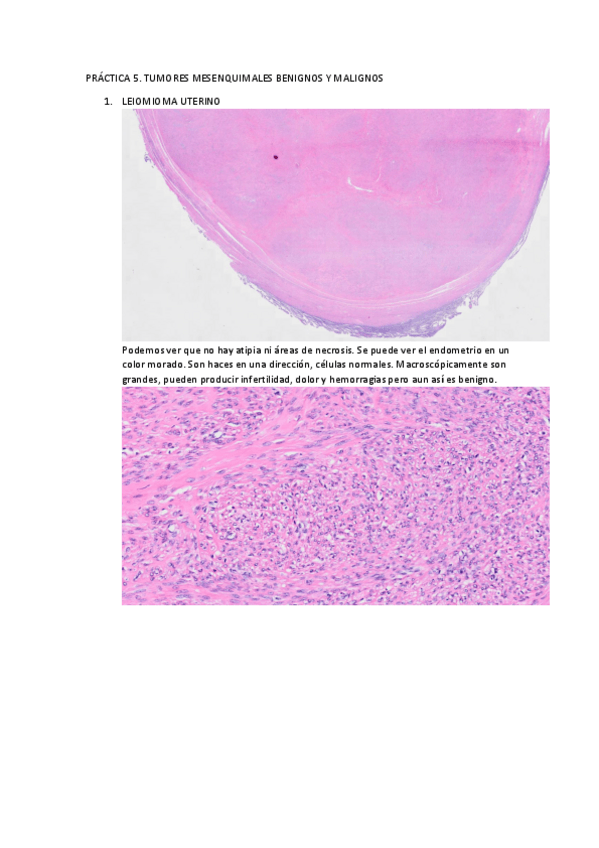

He publicado nuevos practicas de 2º Anatomía Patológica: PRÁCTICAS

PRACTICA-5.pdf